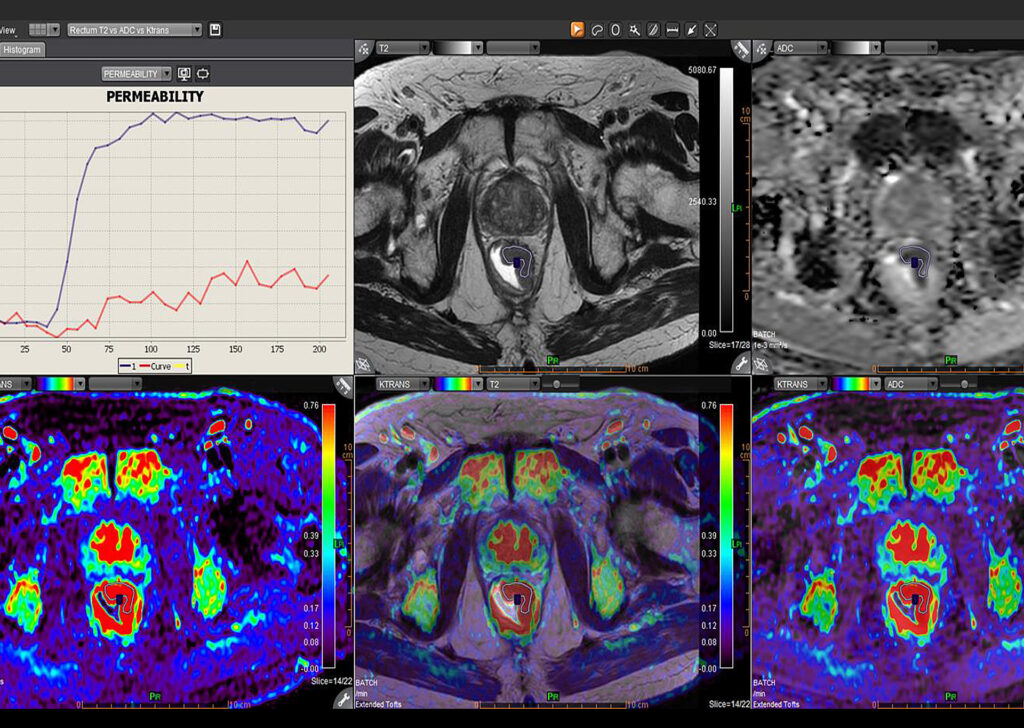

MR Body Full

MR Head and Neck, MR Breast, MR Prostate, MR Rectum, MR MSK, MR Female Pelvis, Advanced Multiparametric Analysis, Dynamic Contrast Enhanced Permeability, Diffusion Weighted Imaging, Kinetics, Longitudinal Analysis, Intravoxel Incoherent Motion, Metabolic, and Onco-Inflammatory.

MR Rectum

Olea MR Rectum application workflow offers efficient multi-step assisted post-processing and 3D visualization for rectal pathologies.